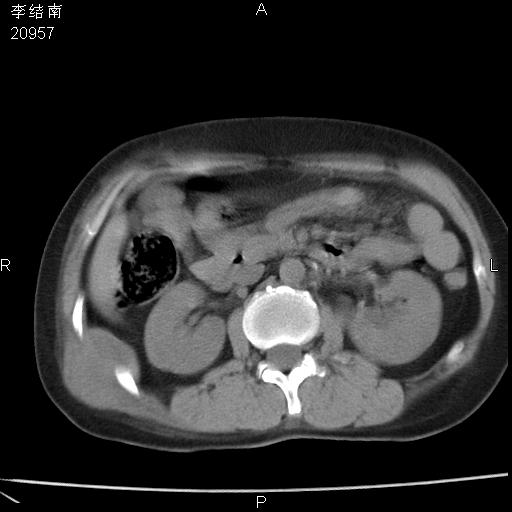

患者女,45岁,以右侧腰部包块来就诊,局部有压痛,皮肤颜色正常。因为是熟人扫的范围较大,患者有胆结石,胆源性胰腺炎病史。请大家看看,有手术病理。

可能大家觉得片子的质量不好,当时是做下腹部扫描,所以没有常规喝水,右腹壁的病灶当时是,密度不均有钙化影,局部骨质没见破坏,肝脏应该是受压的表现,所以当时考虑为腹壁的良性占位,各位老师考虑的神经源性肿瘤,我当时还真没想到,胰腺是胰腺炎治疗后改变.膈脚旁的混杂密度包快不好考虑什么,到上级医院做增强(腹部)+肺部平扫后,发现腹壁的病灶呈不均匀性强化局部可见囊性灶,当时考虑为腹壁结核,最具戏剧性的是膈脚旁的混杂密度灶确是胃的一部分,而腹壁的病灶确是脂肪瘤(简直不可思议)但是我亲眼所见在我们县医院开的.

很不好意思 ,患者后来手术切口裂开,临床医生作了病理证实是腹壁结核。

[病理诊断] CT13183腹壁结核!